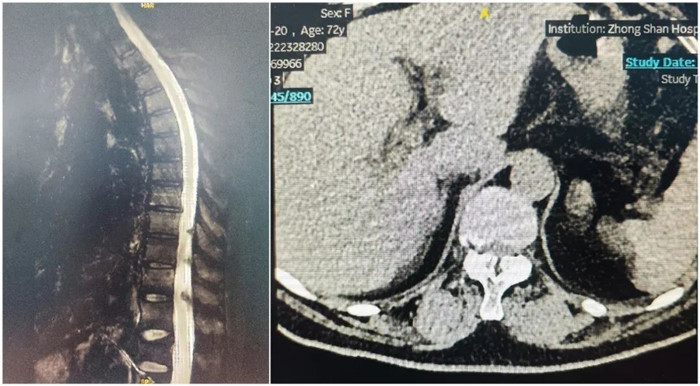

病例一

患者:女性,73歲

術(shù)式:胸腰椎椎間融合+椎板減壓+椎管擴(kuò)大成型+脊髓和神經(jīng)根粘連松解術(shù)

患者兩年前出現(xiàn)左側(cè)胸背部皮膚感覺麻木,有束帶感,左上臂皮膚感覺麻木,否認(rèn)肌力減退,胸平掃椎CT示:胸椎序列正常,生理彎曲存在,椎體邊緣骨質(zhì)增生,椎間盤略退變,T7-T9黃韌帶增生并伴骨化,壓迫內(nèi)膜囊,椎管狹窄。影像診斷:黃韌帶骨化。

術(shù)前影像